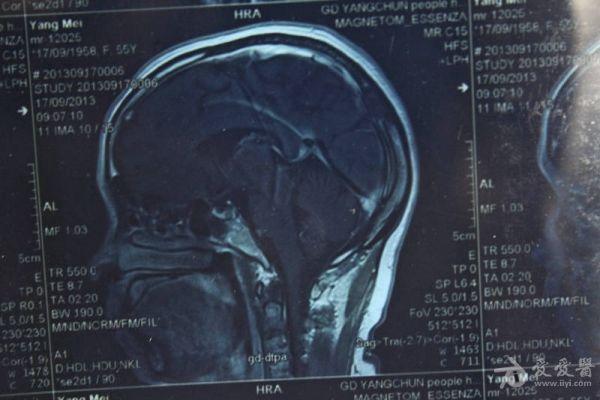

脑部占位病变CT,MRI图片,请帮忙诊断

最近感图样,无其它脑病病史

磁共振没有平扫,增强矢状位没找到病灶。像脑膜瘤。

考虑脑膜瘤!!

图片不是很清楚,应该是脑膜瘤!